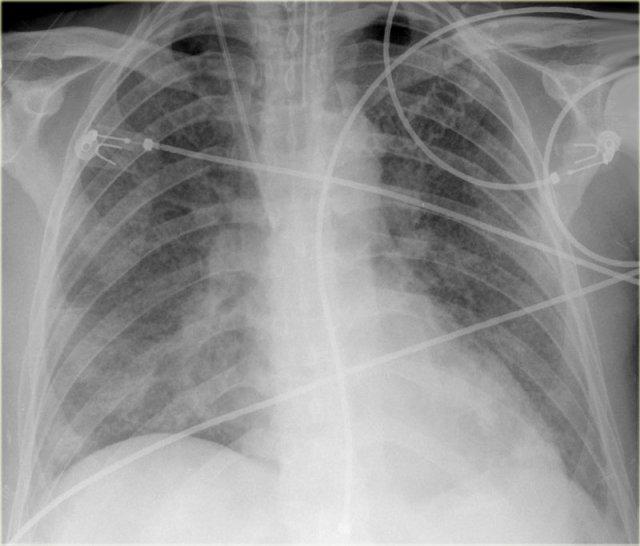

Bên trái là hình ảnh bệnh nhân nhập viện với khó thở nặng do suy tim cấp.

Các dấu hiệu sau đây gợi ý suy tim: phù phế nang với đông đặc quanh rốn phổi và dấu hiệu phế quản hơi (mũi tên vàng); tràn dịch màng phổi (mũi tên xanh lam); tĩnh mạch đơn nổi bật và độ rộng cuống mạch máu tăng (mũi tên đỏ) và bóng tim to (đầu mũi tên).

Sau điều trị, chúng ta vẫn có thể thấy bóng tim to, tràn dịch màng phổi và tái phân phối lưu lượng máu phổi, nhưng phù nề đã được giải quyết.